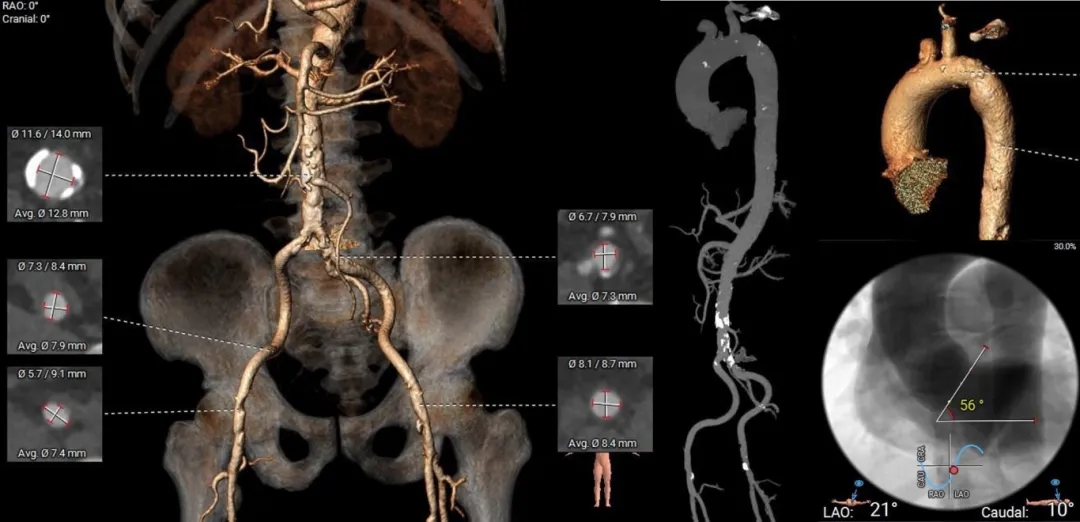

左室增大,瓣环夹角56°,非横位心。

外周血管未见明显迂曲,腹主动脉少量钙化瓣环

心尖入路为第五肋间

外周入路评估

心尖入路评估

入路选择:心尖为主入路;右侧股动脉辅入路